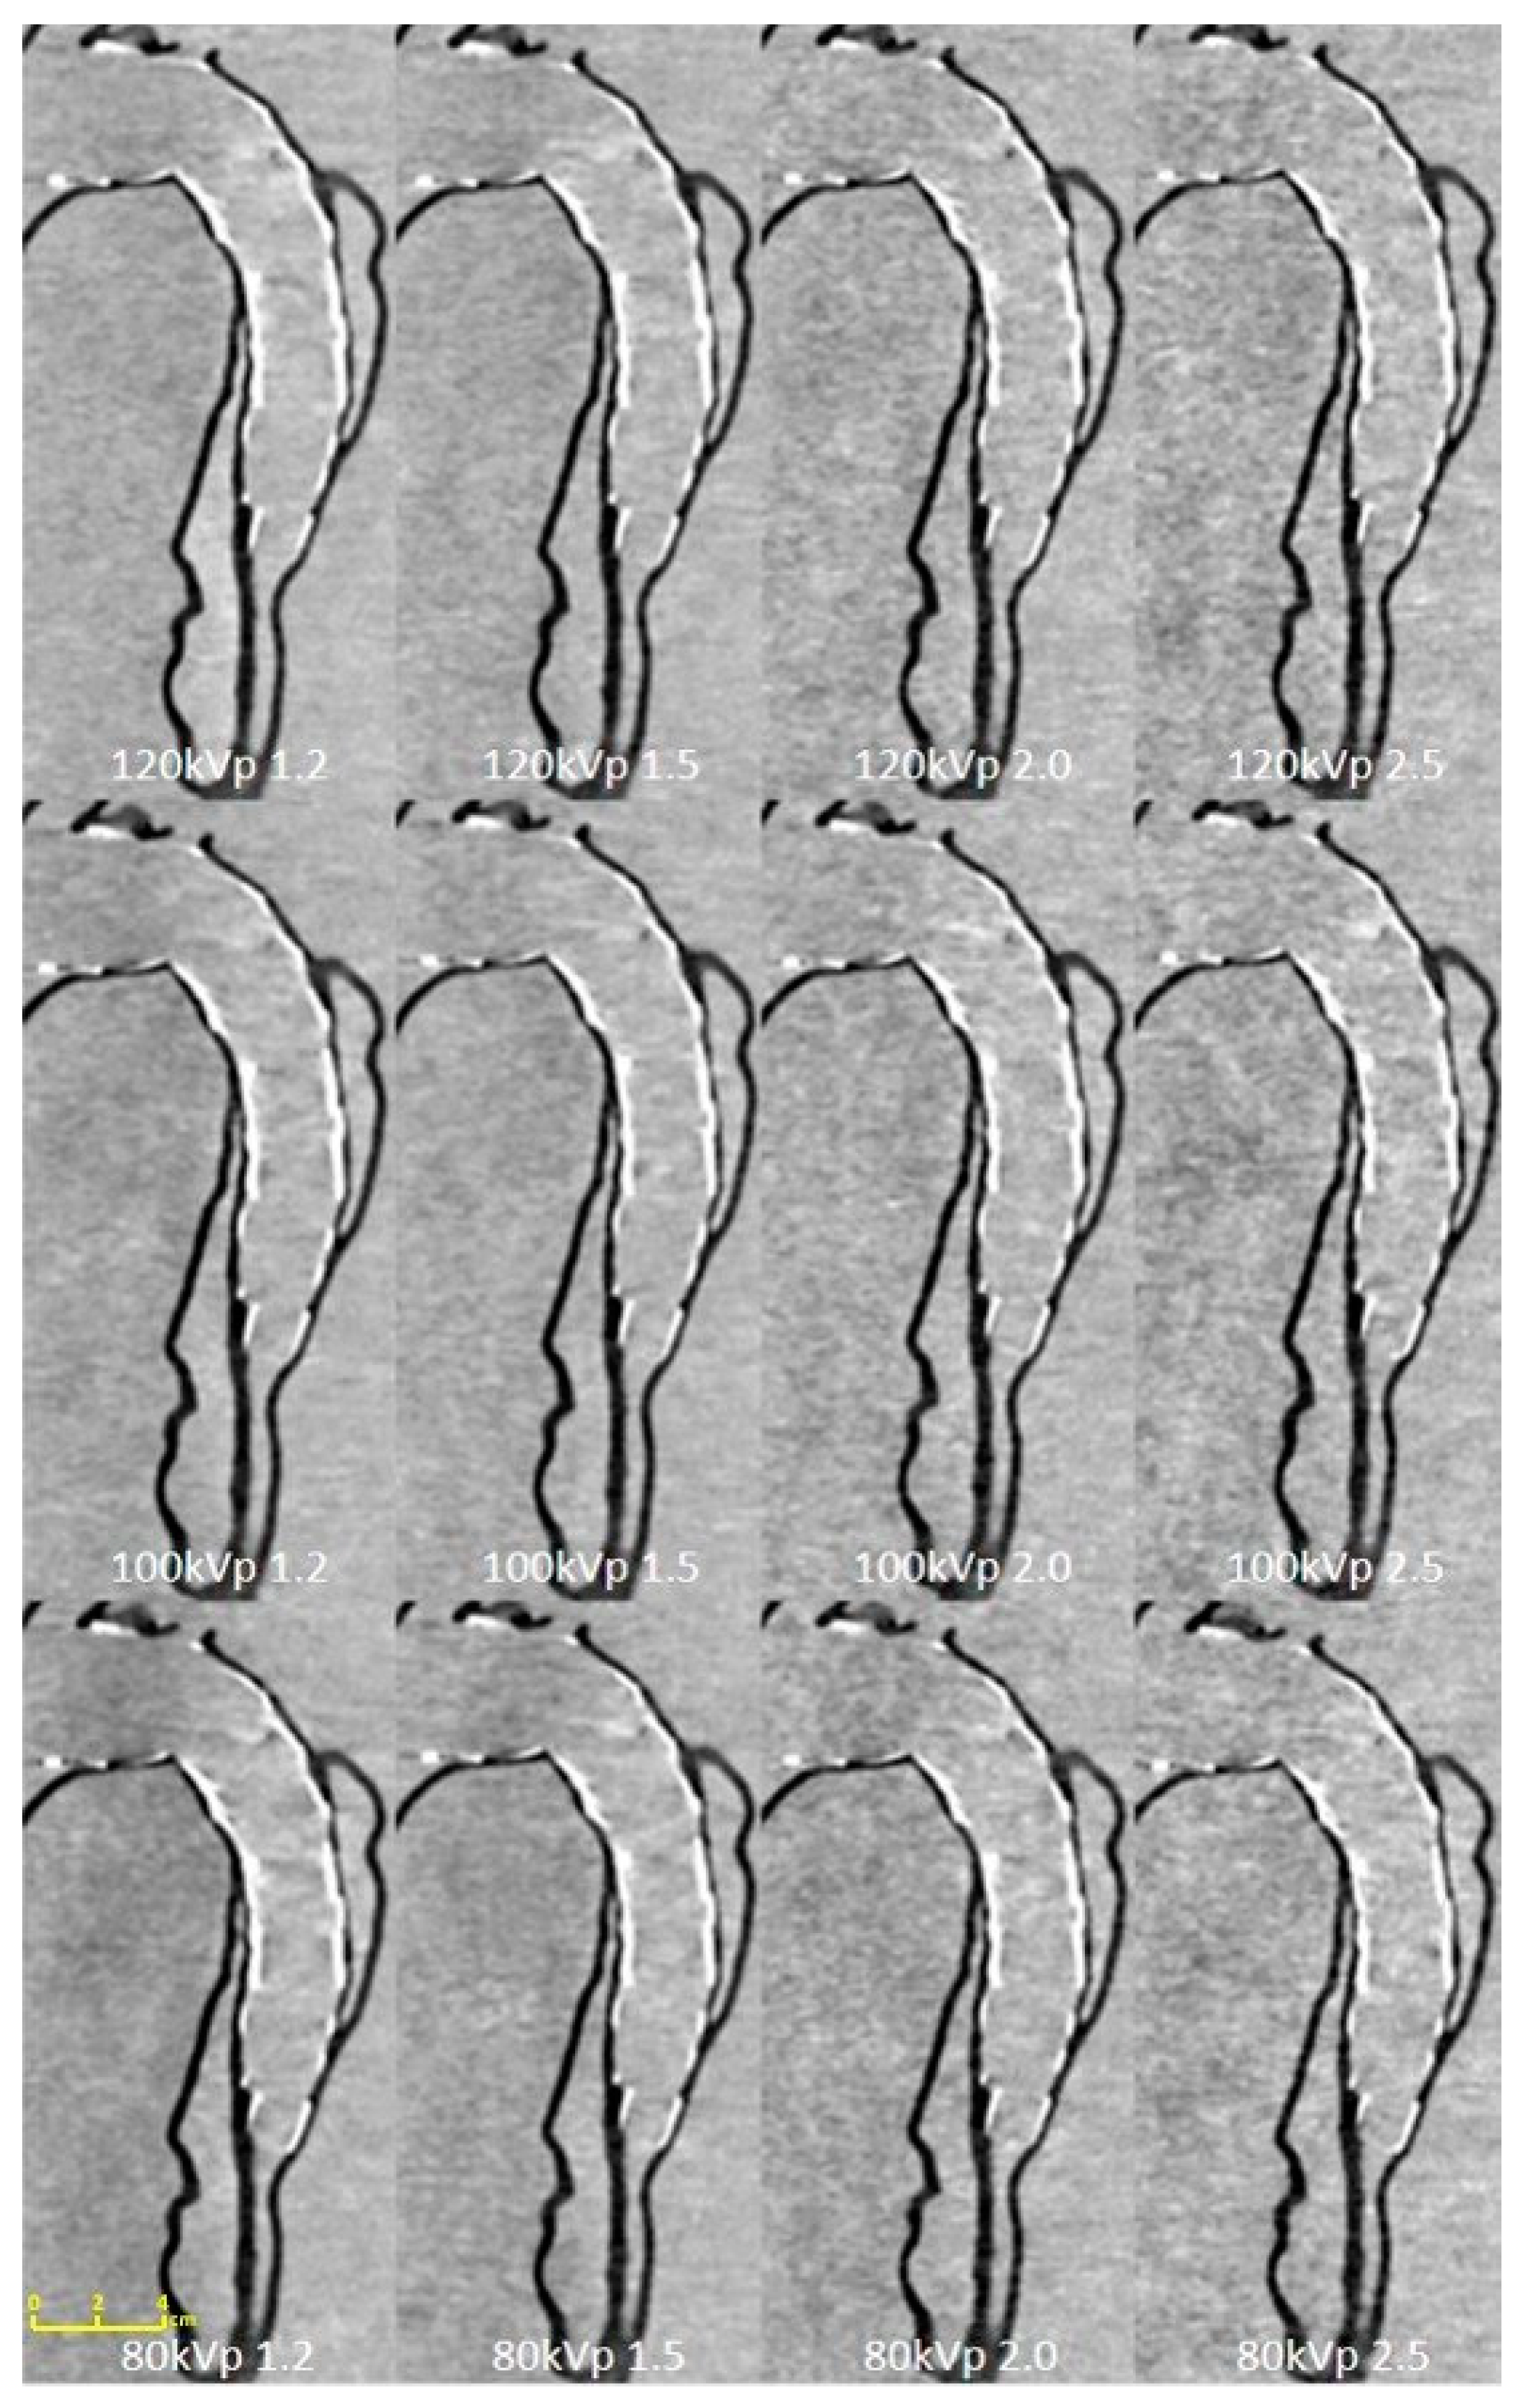

| Tube Voltage | 80 kVp | 100 kVp | 120 kVp | |||||||||

|---|---|---|---|---|---|---|---|---|---|---|---|---|

| Pitch Value | 1.2 | 1.5 | 2.0 | 2.5 | 1.2 | 1.5 | 2.0 | 2.5 | 1.2 | 1.5 | 2.0 | 2.5 |

| True lumen of proximal descending aorta | 23.93 ± 9.34 | 20.30 ± 1.69 | 19.64 ± 1.03 | 13.70 ± 1.42 | 27.60 ± 1.47 | 22.19 ± 2.14 | 19.14 ± 3.75 | 12.60 ± 0.38 | 25.64 ± 4.69 | 25.10 ± 2.74 | 19.93 ± 0.67 | 19.23 ± 3.74 |

| False lumen of proximal descending aorta | 24.70 ± 10.66 | 23.40 ± 0.90 | 20.86 ± 1.98 | 21.34 ± 2.08 | 24.18 ± 2.86 | 23.82 ± 0.64 | 16.63 ± 3.31 | 17.04 ± 1.24 | 26.18 ± 2.44 | 27.61 ± 3.93 | 22.06 ± 1.51 | 24.00 ± 2.94 |

| True lumen of middle descending aorta | 25.29 ± 7.43 | 25.10 ± 3.58 | 18.66 ± 1.19 | 16.62 ± 1.28 | 25.65 ± 2.16 | 25.91 ± 0.29 | 14.74 ± 0.58 | 18.40 ± 1.92 | 23.68 ± 2.33 | 26.21 ± 0.26 | 20.61 ± 1.24 | 19.81 ± 1.04 |

| False lumen of middle descending aorta | 18.12 ± 2.80 | 22.13 ± 1.54 | 10.11 ± 0.60 | 12.47 ± 0.54 | 20.86 ± 2.23 | 26.27 ± 3.77 | 15.62 ± 0.77 | 12.16 ± 1.16 | 20.15 ± 1.29 | 29.91 ± 4.84 | 14.03 ± 0.80 | 13.53 ± 0.51 |

| CTDIvol (mGy) | 0.07 | 0.08 | 0.06 | 0.06 | 0.1 | 0.1 | 0.08 | 0.07 | 0.11 | 0.1 | 0.08 | 0.07 |

| DLP (mGy/cm) | 2.8 | 2.9 | 2.2 | 2.1 | 3.9 | 3.8 | 2.7 | 2.4 | 4.1 | 3.8 | 2.8 | 2.5 |

| Effective dose (mSv) | 0.04 | 0.04 | 0.03 | 0.03 | 0.05 | 0.05 | 0.04 | 0.03 | 0.06 | 0.05 | 0.04 | 0.04 |